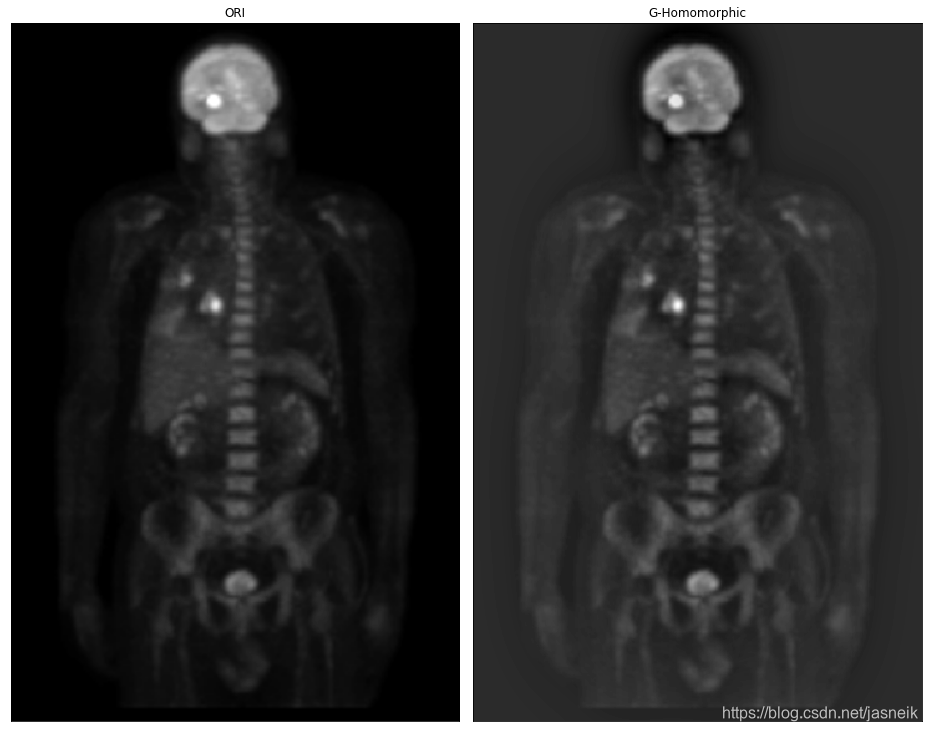

# 高斯同态滤波器,根据推导过程应用,但得到不好的图像,然后上面的直接应用的话,就算改变不同的参数,变化也不是很大

img_ori = cv2.imread('DIP_Figures/DIP3E_Original_Images_CH04/Fig0462(a)(PET_image).tif', -1)

M, N = img_ori.shape[:2]

img_ln = np.log(img_ori+1e-8)# 填充

fp = pad_image(img_ln, mode='constant')

fp_cen = centralized_2d(fp)

fft = np.fft.fft2(fp_cen)# 滤波器

GHF = gauss_homomorphic_filter(fp, fp.shape, rl=0.8, rh=1, c=3, radius=20)# 滤波后的图像

img_new = frequency_filter(fft, GHF)

img_new = img_new[:M, :N]

img_new = np.exp(img_new)img_new = np.clip(img_new, 0, img_new.max())

img_res = np.uint8(img_new / img_new.max() * 255)plt.figure(figsize=(13, 14))

plt.subplot(1, 2, 1), plt.imshow(img_ori,'gray'),plt.title('ORI'), plt.xticks([]), plt.yticks([])

plt.subplot(1, 2, 2), plt.imshow(img_new,'gray'),plt.title('G-Homomorphic'), plt.xticks([]), plt.yticks([])

plt.tight_layout()

plt.show()